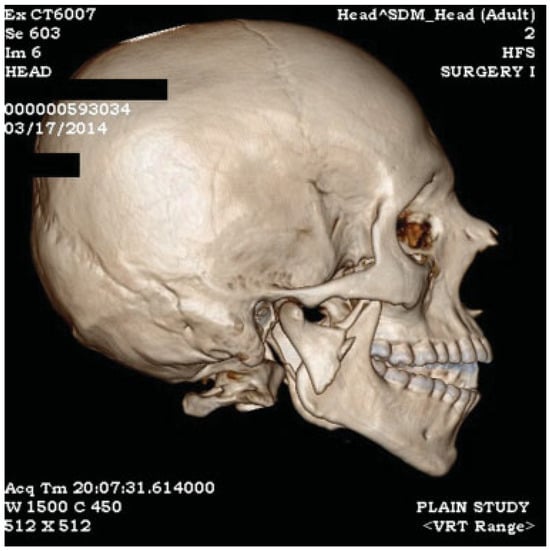

Figure 1.

(a) Coronal section through temporomandibular joint, (b) PA mandible shows laterally displaced condyle.

Figure 2.

3D reconstruction image showing laterally displaced condyle with shortening of posterior ramal height with premature occlusion of posterior teeth resulting in anterior open bite.